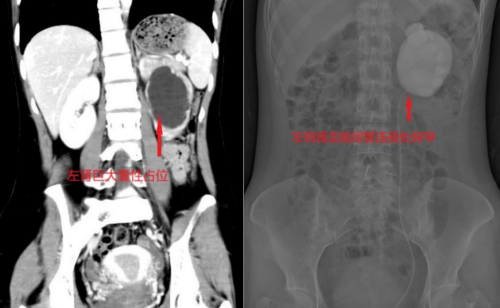

“肾积水?”这个陌生的词让张柔心里一沉。她立即来到长沙市中心医院泌尿外科门诊就诊。CT三维重建清晰显示,她的左侧肾盂被尿液撑得像一个巨大水囊,肾皮质已被压迫变薄;而进一步的“逆行尿路造影”明确了病因——肾盂与输尿管连接的“关口”出现严重狭窄,造影剂通过艰难,上游的肾脏已长期“泡”在积液中。

面对张柔的病情与紧迫的面试安排,泌尿外科一区团队在主任傅发军的带领下制定了周密的微创手术方案。术前影像提示,其肾盂输尿管连接处可能受一条异位血管压迫。团队决定施行“腹腔镜左侧肾盂输尿管成形术”。术中,周建军主任医师通过几个微小切口,巧妙经自然组织间隙抵达病灶区域,避免传统手术需大面积游离肠道的过程,最大程度减少了对腹腔的干扰。术中探查发现,一条横跨的异位血管紧紧压迫输尿管,这正是导致狭窄的“元凶”。医生精细解除了血管压迫,修剪扩张的肾盂,重新吻合尿路通道,彻底疏通了“堵塞点”。

得益于微创手术创伤小、疼痛轻的优势,结合加速康复外科理念,张柔术后恢复顺利。手术当天即可下床活动,次日经评估拔除引流管,复查显示其左肾积水显著消退,肾功能逐步恢复,腰部不适基本消失。张柔精神状态良好,最终如期参加面试并成功获得心仪职位。